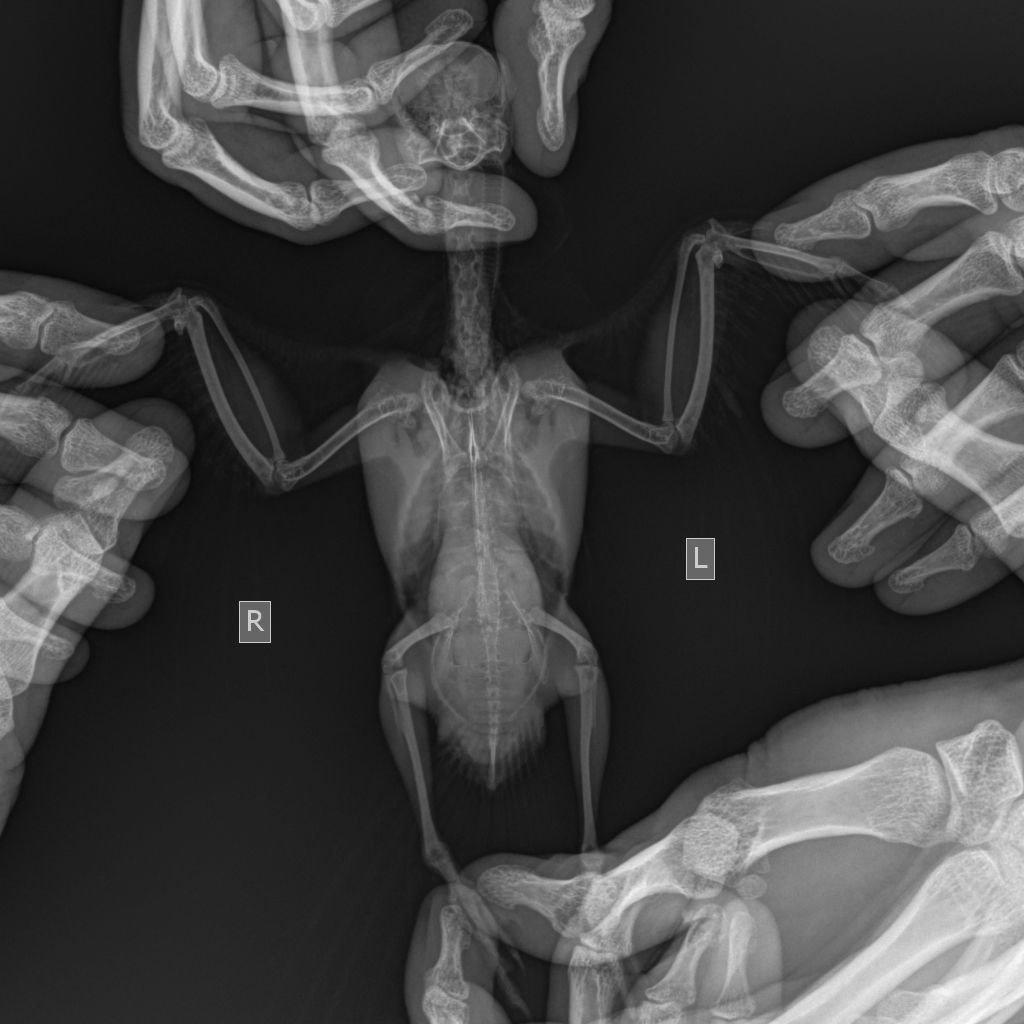

Помогите расшифровать рентген уже мертвой птицы

Здравствуйте, подскажите пожалуйста, знающие люди по рентгену и анализам что могло быть с птичкой? Умерла пару дней назад...

1. Корелла

2. 5 лет, самка

У птицы сочетанная респираторная инфекция, скорее всего застарелая )т.к. легкие хоть и с признаками поражения, но умеренно, возможно есть фиброз, особенно справа).

Печень увеличена, имеет неровную дорсальную поверхность, целомическая поость уменьшена. Возможно имеется НО (может кисты) яичника или почки...